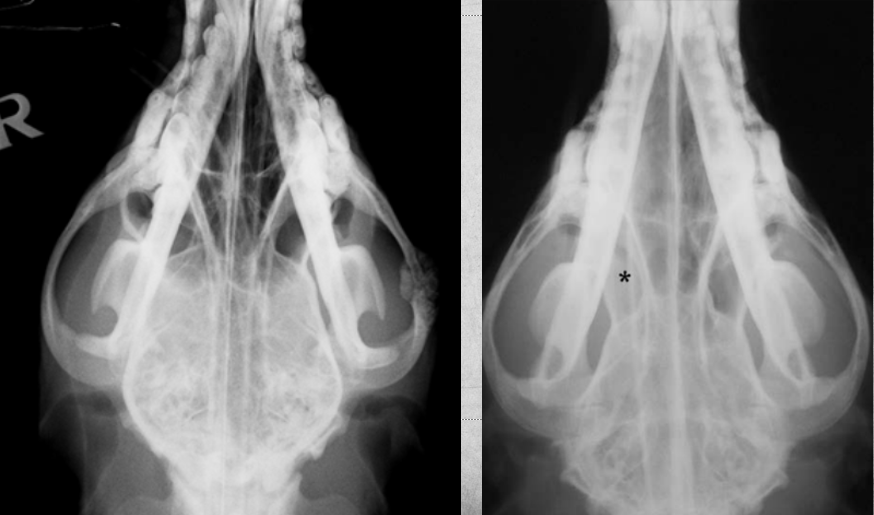

19

Q

identify pathology

A

calvarium neoplasia in left image

mandibular neoplasia in right side image